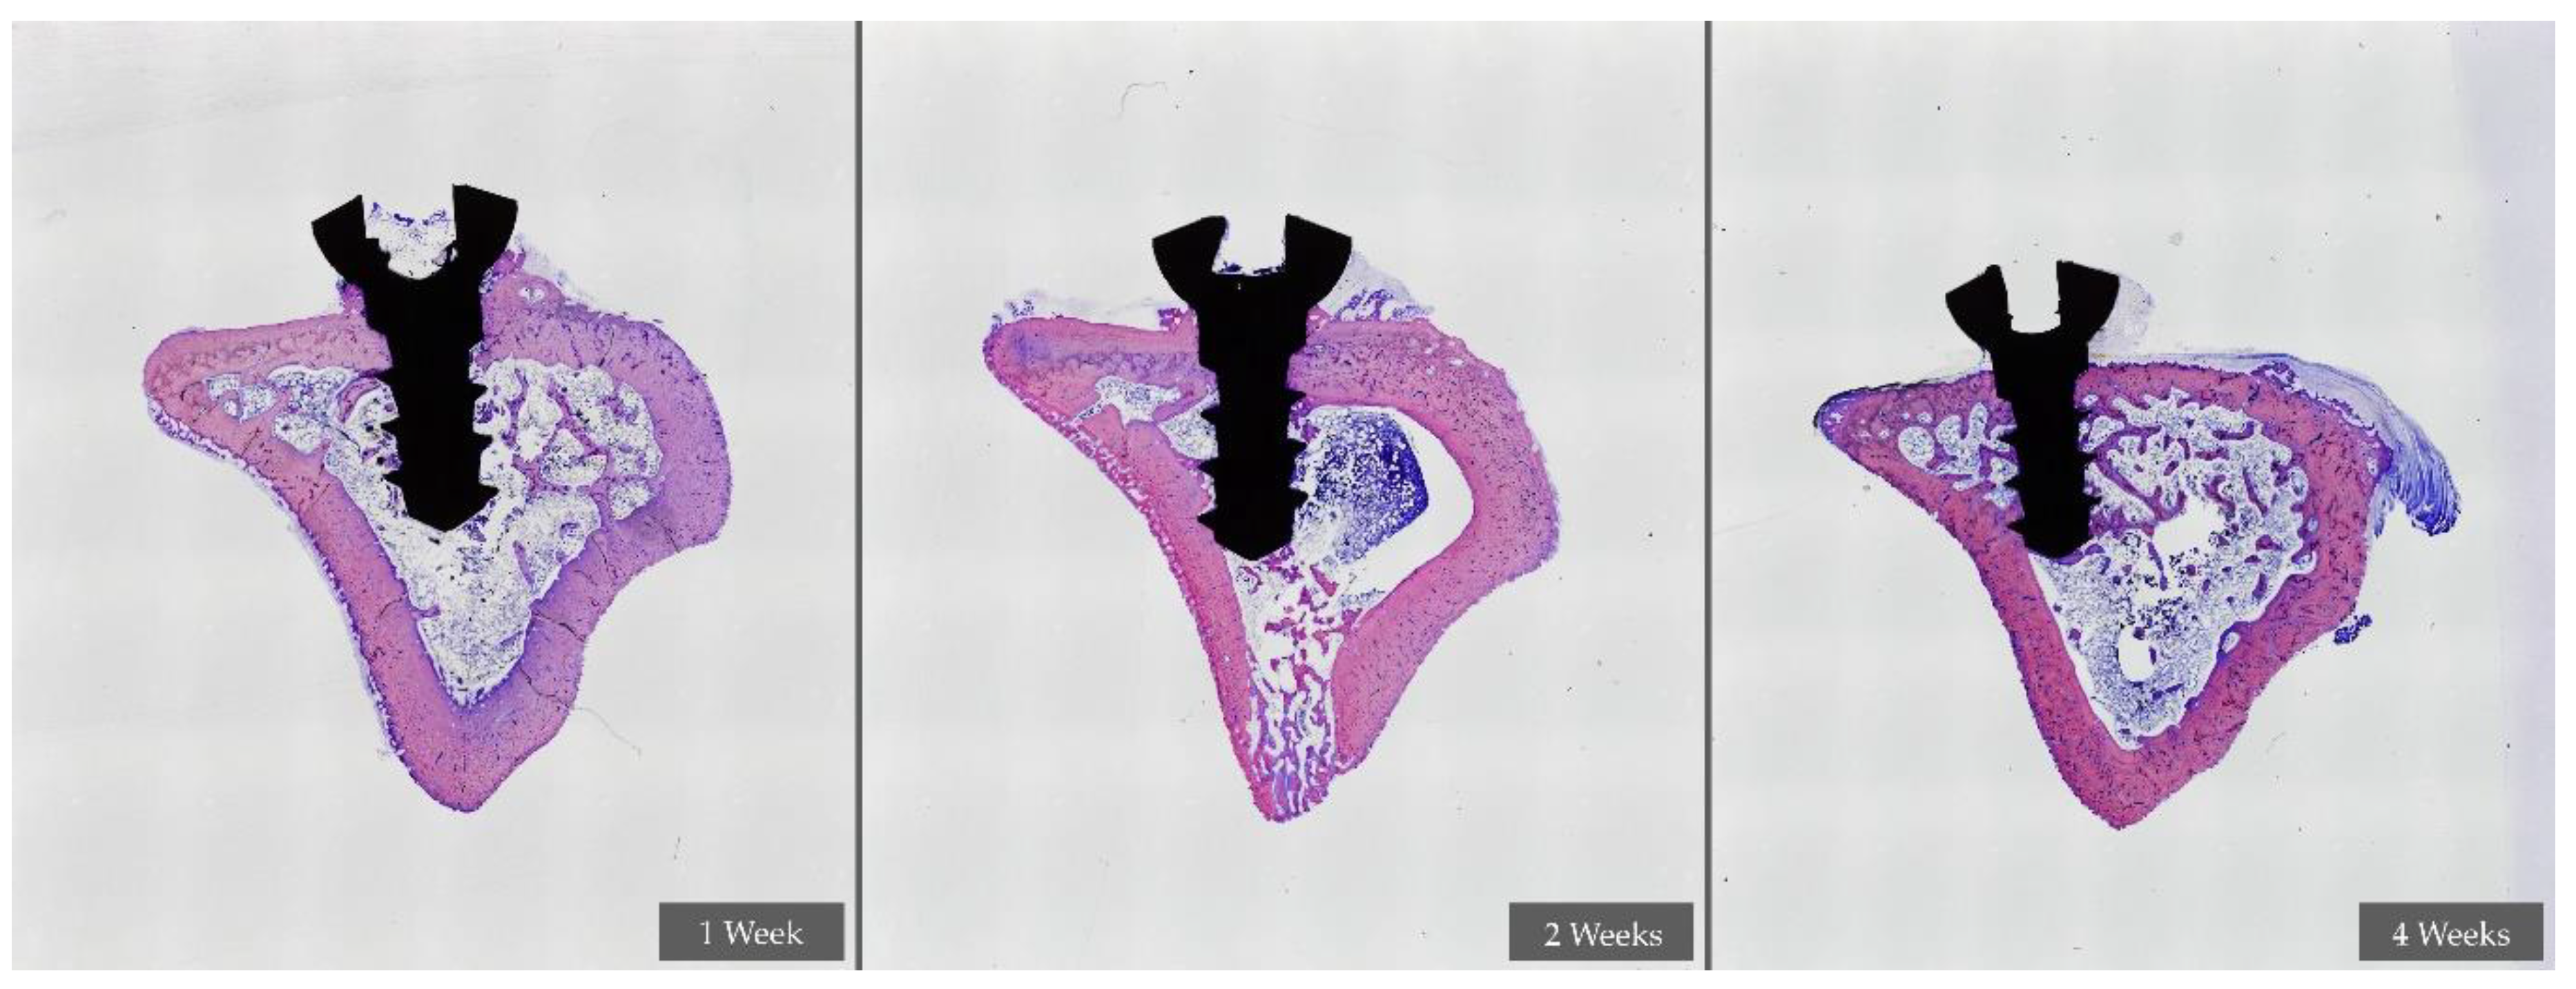

2.7.3. Histological Preparation

- -

- Block preparation

- -

- Sheet preparation and evaluation